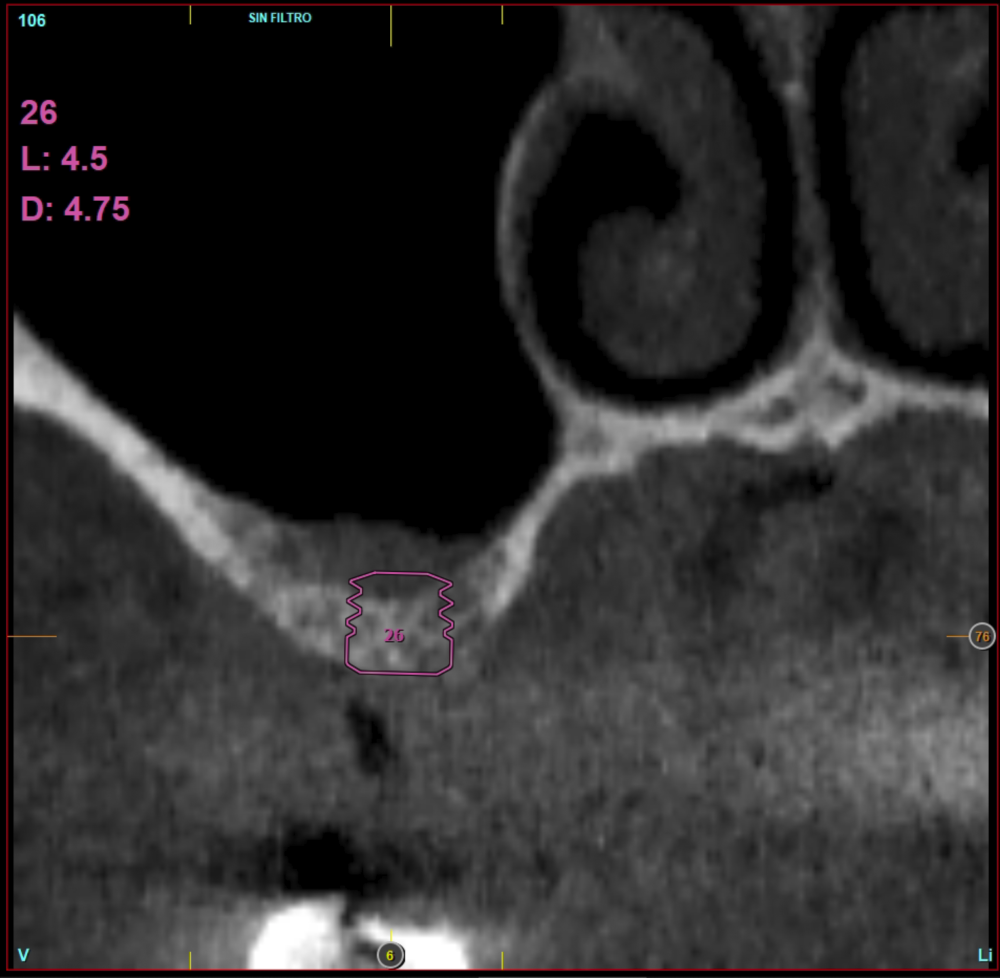

Material and method. A retrospective study has been carried out in patients in whom extra-short implants (4.5 and 5.5 mm length) were inserted directly by transcrestal elevation with residual ridges between 2 and 3 mm. The implant was the analysis unit for the descriptive statistics regarding location, implant dimensions, and radiographic measurements. The patient was the measurement unit for the analysis of age, sex and medical history. The main variable was the gain in height over the apex of the implant after 6 months of the surgery and one year after the load comparing both measurements and as secondary variables the biological complications and the implant failure were recorded.

Results. Ten patients who met the inclusion criteria were recruited and 20 implants were inserted. The mean residual bone volume height was 3.1 mm (+/- 0.3 mm with a range elevation above the apex of the implant in millimetres is of 2.8 mm (+/- 0.99 range 1.9 -5 mm). In the control cone-beam after one year of the studied load of the implants, the bone gain achieved was maintained, with no decrease in the volume gained, only three cases showed a decrease of between 0.4 and 0.5 mm of the initial volume at the end. No implants failed in the follow-up period and no biological complications were found in the surgery.

In this type of approach to the sinus, an important point is the stability of the grafted bone, located above the apex of the implant and with a bone tissue little vascularized (as usually occurs in these large atrophies with low density), so assessing what happens with the bone volume gained by this long-term procedure is also a key fact26,27. The mineralization of the bone graft and its maintenance once the implant loading is performed can make the difference in the success of the technique, especially in increasingly extreme cases. Therefore, the material used as a graft and the surface of the implant are two factors to take into account when performing this type of procedure28-31. Hydrophilic and osteoconductive surfaces in implants are of vital importance in these complex cases, as well as the filling materials that stimulate the formation of new bone28-31. The implants with UnicCa (Biotechnology Institute, Vitoria, Spain) surface, have a superhydrophilic surface. It is a very rough surface (Optima), with a calcium ions layer. This implies that the contact of blood and plasma with all points of the surface increases to the maximum the active surface for regeneration, by being completely coated with fluids due to its high capillarity. In the following series of clinical cases, patients treated by transcrestal sinus lift, with extra-short and ultra-short implants (4.5 and 5.5 mm), BTI (Biotechnology institute), of internal connection and universal plus platform in residual bone heights below 3 mm, studying the behaviour of implants regarding their survival as well as the maintenance of the bone volume achieved in the crestal elevation.